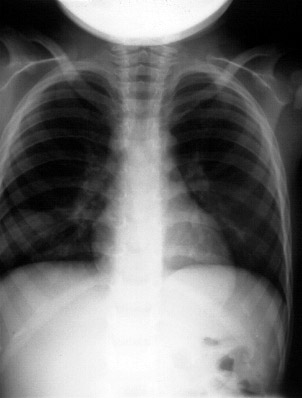

Key takeaway: In febrile children with a benign abdominal exam, right lower-lobe pneumonia is a classic cause of RUQ abdominal pain—obtain a chest radiograph when suspected.

This child presented with complaints of fever and RUQ abdominal pain. The abdominal exam was benign. What's causing the upper abdominal pain?

This high-miss item tests recognition that lower-lobe pneumonia can present with abdominal pain, particularly RUQ pain, in children due to diaphragmatic irritation and shared innervation. A benign abdominal exam with fever should prompt consideration of chest pathology, and CXR often reveals a basilar infiltrate.

The keyed answer (pneumonia) is correct and guideline-concordant. ACR Appropriateness Criteria (2023) for suspected appendicitis in children explicitly notes pneumonia as an extra-abdominal cause of abdominal pain and supports chest imaging when clinical features suggest it. AAP Pediatrics in Review (2021) likewise emphasizes lower-lobe pneumonia as a common mimic of acute abdomen in pediatrics.

| pneumonia | Recognition of extra-abdominal cause of abdominal pain | Correct: Lower-lobe pneumonia commonly causes RUQ pain in children; CXR shows basilar infiltrate. |

In a febrile child with RUQ or right lower quadrant pain and a benign abdominal exam, always consider and image for right lower-lobe pneumonia.